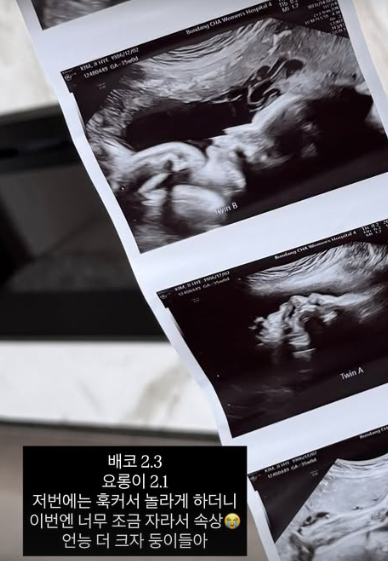

이어 "배코 2.3kg 요롱이 2.1kg 저번에는 훅 커서 놀라게 하더니 이번엔 너무 조금 자라서 속상. 언능 더 크자 둥이들아"라고 전했다.